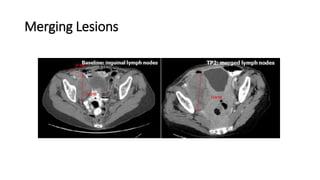

Merging Lesions

• If target lesions become confluent, calculate the

longest diameter of the resulting lesion.

• The resulting longest diameter accounts for the

contribution of ALL involved target lesions to the sum

of diameters (SOD)